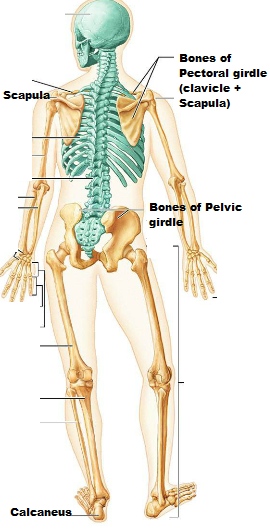

Anatomy of a long bone:

- Shaft is called - ___________

- diaphysis

- A fibrous membrane covering the bone surface -________

periosteum

- Fibers of the periosteum penetrating into the bone- ___________________________

Perforating (Sharpey's) fibers

Blood vessel and nerves travel through the ___________ and invade the bone

periosteum

- end of the long bone - _____________________

epiphysis

- A glassy hyaline cartilage that covers the epiphyseal surface in place of the periosteum - _________________

articular cartilage

Articular cartilage prevents _________ at joint surfaces.

friction

A thin area of hyaline cartilage that provides for longitudal growth of the bone during youth.

Epiphyseal plate

Once the bone has stopped growing, the plates are replaced with bone and appear as thin and barely discernible remnants-

Epiphyseal line

In adults, The central cavity or the medullary cavity of the shaft is a storage region for adipose tissue or _____________ marrow

yellow marrow

In infants, the central cavity or the medullary cavity of the shaft is involved in forming blood cells, so __________ marrow is found.

red marrow

In adults the red marrow is confined to the interior of ___________.

Epiphyses (occupies the spaces b/w the trabeculae of spongy bone)

Endosteum covers the -

__________ of spongy bones

lines the canals of _________ bone

trabeculae

canals of compact bone

Identify the parts of the long bone